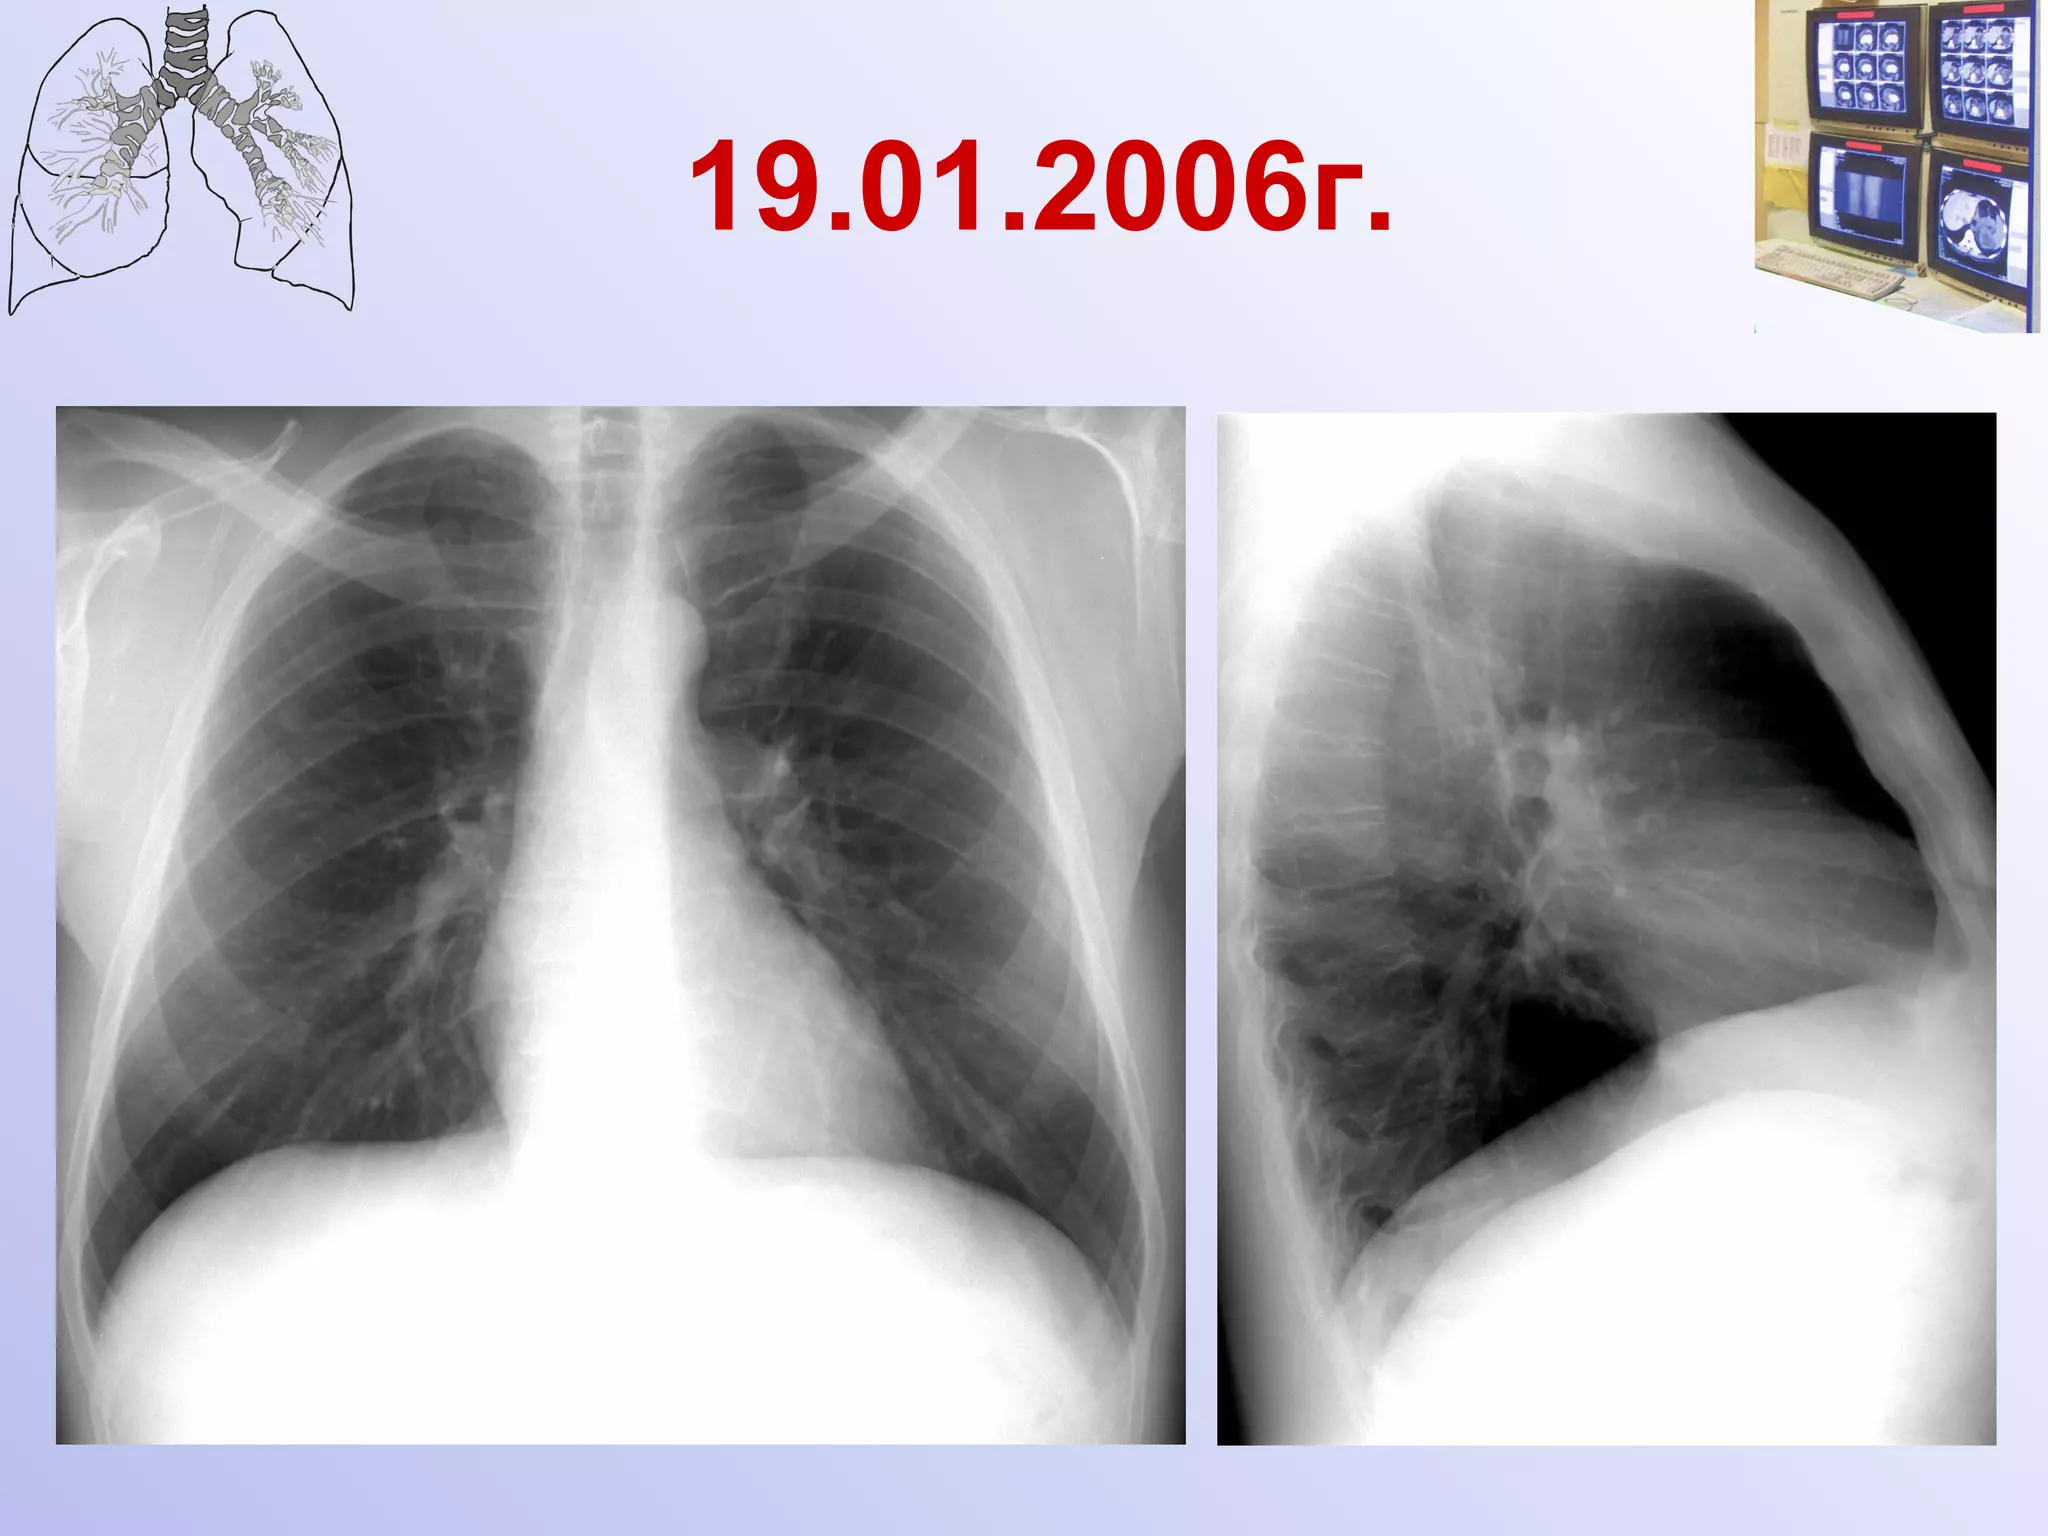

Инвазивный микоз Развитие патологического процесса в легких за 4 дня Ершов

19.01.2006г.

19.01.2006г. Малоинтенсивный очаг уплотнения в третьем межреберье справа